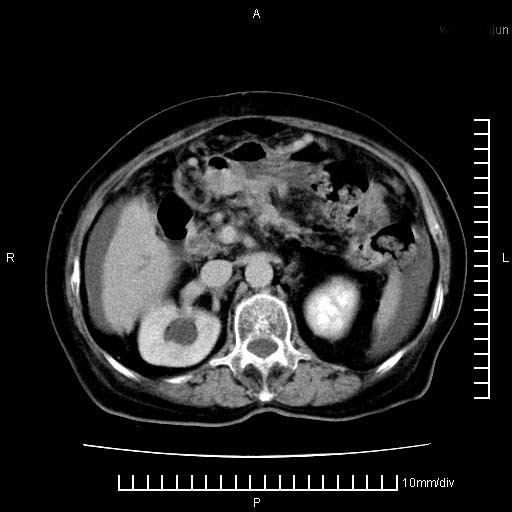

标题: CT28280:腹部增强:女性,80岁

上腹疼痛月余,外院核磁诊断胰腺癌。现临床示右下腹可明显触及包块,可片子上怎么没有看到?

胰腺体部癌累及周围器官,腹膜、粘连

胰腺体部癌累及周围器官,腹膜、粘连,临床摸到的可能是粘的组织

胰腺结构模糊,胰尾部见囊性包块,周围脂肪密度增高,左肾前筋膜增厚,胸水、腹水。不符合胰腺ca伴腹膜腔转移。考虑胰腺炎伴假性囊肿形成、胸腹腔积液。

1)考虑胰腺癌并胰腺假性囊肿形成。2)肝内低密度灶,不排除转移。3)右肾盂积水。4)腹水。5)右侧胸腔积液并右肺下叶部分膨胀不全。